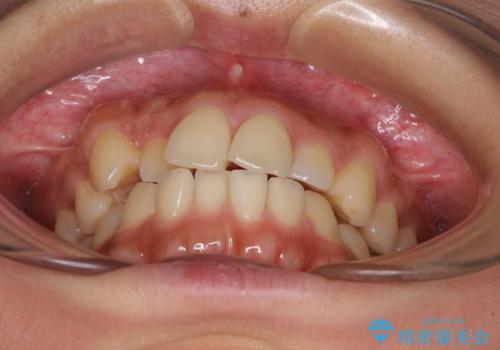

【モニター】歯列が狭くデコボコが気になる 急速拡大装置を用いたインビザライン矯正

- 奥歯の咬み合わせと治療を放置したまま奥歯を気にして来院された患者様です。

上顎骨の幅が下顎骨よりも小さいので、拡大装置により骨幅を広げて上下関係を改善し、その後インビザラインにて歯並びを整えることとしました。

上下の骨幅を改善したことで、スムーズに歯列矯正を行うことができました。

土台のまま放置されていた歯は土台の状態で咬み合っていましたが、急速拡大を行った際に咬み合わせが著しく挙上されたため、その際に土台を大きくすることで咬み合う歯との距離を確保しました。